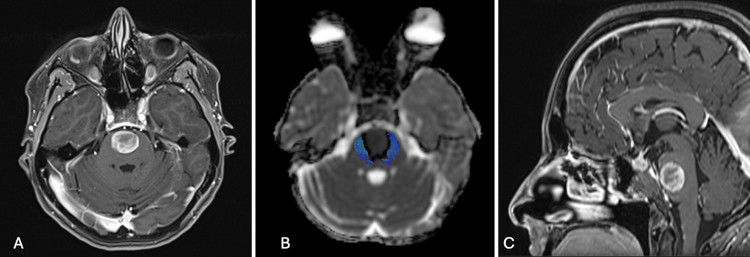

Observations: The authors report the case of a 54-year-old woman with a ventral pontine cavernous malformation (CM) presenting with recurrent hemorrhagic episodes, all resolving without neurological sequelae. Based on the anterior midline location of the lesion within the pons and the posterolateral displacement of the corticospinal tracts (CSTs) on preoperative tractography, an EETA was deemed the most suitable approach. Gross-total removal was achieved without neurological worsening or postoperative CSF leakage.

Lessons: This case supports the use of EETA as a safe and effective surgical route for ventral pontine CMs with anterior surface presentation. Accurate preoperative planning, including assessment of CST displacement via diffusion tensor imaging, and direct intraoperative cortical stimualtion are essential for identifying a safe entry point. Although technically demanding and not universally applicable, EETA offers a direct surgical corridor that minimizes neurovascular manipulation and facilitates favorable outcomes in selected cases. https://thejns.org/doi/10.3171/CASE25356.